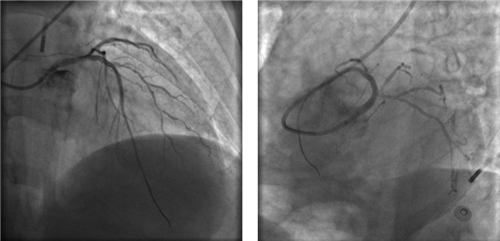

因患者股動(dòng)脈扭曲,導(dǎo)管操控困難,術(shù)者反復(fù)嘗試,以導(dǎo)絲飄進(jìn)左主干,在球囊的支撐下,通過(guò)閉塞段到達(dá)中間支,小壓力擴(kuò)張后造影可見(jiàn)主干末端嚴(yán)重狹窄。隨后小心操控導(dǎo)絲到達(dá)回旋支、前降支,送入球囊擴(kuò)張,嚴(yán)重狹窄的左主干末端被撐開(kāi),左冠血流終于恢復(fù),胡女士暫時(shí)轉(zhuǎn)危為安。

球囊擴(kuò)張后,左冠血流恢復(fù),但左主干末端重度狹窄

左主干末端呈三分叉,前降支、回旋支均存在彌漫性病變,且血管非常細(xì)小,這是一個(gè)相當(dāng)復(fù)雜的左主干分叉病變。冒然植入支架,可能導(dǎo)致支架邊緣夾層、分支閉塞、慢血流等并發(fā)癥,稍有不慎,都會(huì)給患者帶來(lái)災(zāi)難性的后果。心血管內(nèi)科團(tuán)隊(duì)慎重決定,暫不植入支架,在IABP支持下,待血流沖刷冠狀動(dòng)脈,血管痙攣解除、血管擴(kuò)張后,再在IVUS(血管內(nèi)超聲)指導(dǎo)下植入支架。

左冠血流保持通暢

確認(rèn)左冠血流保持通暢,大家懸著的心才稍稍放下。

根據(jù)IVUS檢查結(jié)果,在前降支近中段至左主干植入3枚支架,充分?jǐn)U張后,狹窄完全解除,血流恢復(fù)通暢。

植入3枚支架,血流恢復(fù)通暢